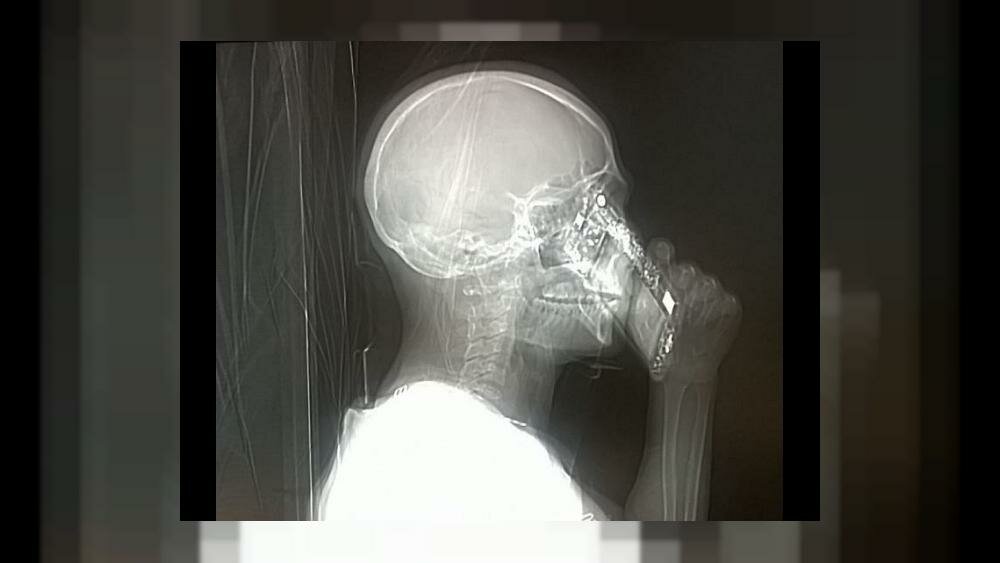

Il rapporto con la tecnologia e in particolare con gli smartphone sta diventando sempre più morboso. Questa volta la storia sembra paradossale,una donna ha risposto al cellulare mentre si stava sottoponendo ad una tac all’ospedale Cardarelli di Napoli.

La paziente ha spiegato:” Avevo portato il cellulare con me per errore”, spiegando che il regolamento lo vieta. Ovviamente, la sua presenza invalida completamente l’esame, ma non ha conseguenze sul paziente. Gli oggetti non assorbono le radiazioni, quindi non è pericoloso tenere vicino il cellulare dopo averlo accidentalmente introdotto all’interno della macchina dei raggi in funzione.

L’esame si è svolto in maniera regolare e non sono stati riscontrati problemi particolari. Il primario Mario Muto si è così espresso sulla bizzarra vicenda: “Mi è sembrato paradossale. Eppure è accaduto davvero. La signora stava parlando al telefono durante la Tac”..